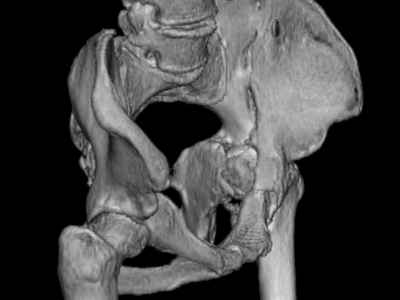

Уважаемые коллеги, возник вопрос по лечению нашей пациентки 60 лет. Около года назад множественная травма: в том числе Т-образный перелом вертлужной впадины. На сегодняшний день сращение отломков имеется на ограниченных участках, имеется дефект задней колонны вертлужной впадины. Движения неплохие, ходит с костылями, приступая на ногу. По мнению эдопротезистов при установке антипротрузионного кольца или октопуса не хватит костного материала и необходимо перед протезированием выполнить реконструкцию впадины, иначе чашка протеза неминуемо выпадет.Просьбы поделиться положительным и отрицательным опытом протезирования в подобных случаях.Возможно ли обойтись без реконструкции?Или лучше с ней?С уважением РАВ.